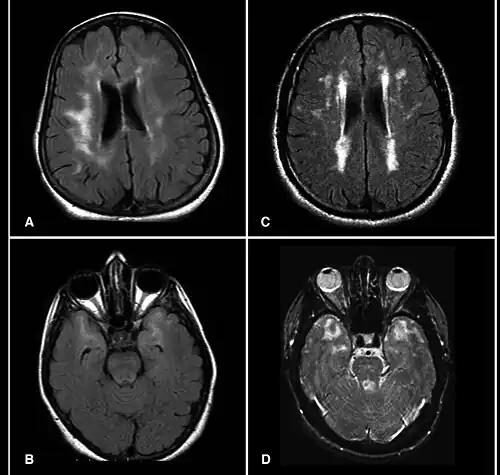

A hyperintensity or T2 hyperintensity is an area of high intensity on types of magnetic resonance imaging (MRI) scans of the brain of a human or of another mammal that reflect lesions produced largely by demyelination and axonal loss. These small regions of high intensity are observed on T2 weighted MRI images (typically created using 3D FLAIR) within cerebral white matter (white matter lesions, white matter hyperintensities or WMH)[1][2] or subcortical gray matter (gray matter hyperintensities or GMH). The volume and frequency is strongly associated with increasing age.[2] They are also seen in a number of neurological disorders and psychiatric illnesses. For example, deep white matter hyperintensities are 2.5 to 3 times more likely to occur in bipolar disorder and major depressive disorder than control subjects.[3][4] WMH volume, calculated as a potential diagnostic measure, has been shown to correlate to certain cognitive factors.[5] Hyperintensities appear as "bright signals" (bright areas) on an MRI image and the term "bright signal" is occasionally used as a synonym for a hyperintensity.

Hyperintensities are commonly divided into 3 types depending on the region of the brain where they are found. Deep white matter hyperintensities occur deep within white matter, periventricular white matter hyperintensities occur adjacent to the lateral ventricles and subcortical hyperintensities occur in the basal ganglia.